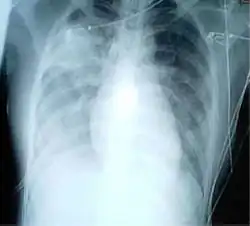

Le , en Chine les critères de diagnostic de la maladie changent, ce qui augmente le nombre de cas. En effet, débordés, les hôpitaux du Hubei se basaient sur une radio des poumons, sans analyse de prélèvements ; soigner et isoler plus tôt les malades était prioritaire, et les résultats du test nécessitent 48 heures alors que le diagnostic radiographique est immédiat[184]. De plus, le système de santé chinois ne rembourse les soins qu'aux malades testés positifs. Pour les autres, la facture est de plusieurs milliers voire dizaine de milliers d'euros. Beaucoup hésitaient à se soumettre au test[184].